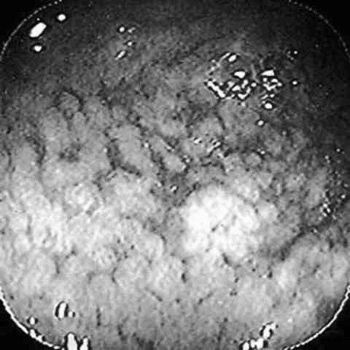

діагностика

Виявляється патологія після дослідження біоптату слизової, яка проводиться в процесі ФГДС. У препараті виявляють характерні змінені клітини, які продукують сульфамуцін. Ця речовина здатна абсорбувати на собі канцерогени, які провокують розвиток онкології.

Також клітини змінюють склад своїх антигенів: з'являється раково-ембріональний антиген (свідоцтво зниження диференціювання клітин), підвищений рівень якого виявляють у крові. В результаті проведених досліджень виставляється діагноз, в формулюванні якого враховуються розміри і місце знаходження метаплазії, наприклад, вогнищева кишкова метаплазія слизової антрального відділу шлунка.